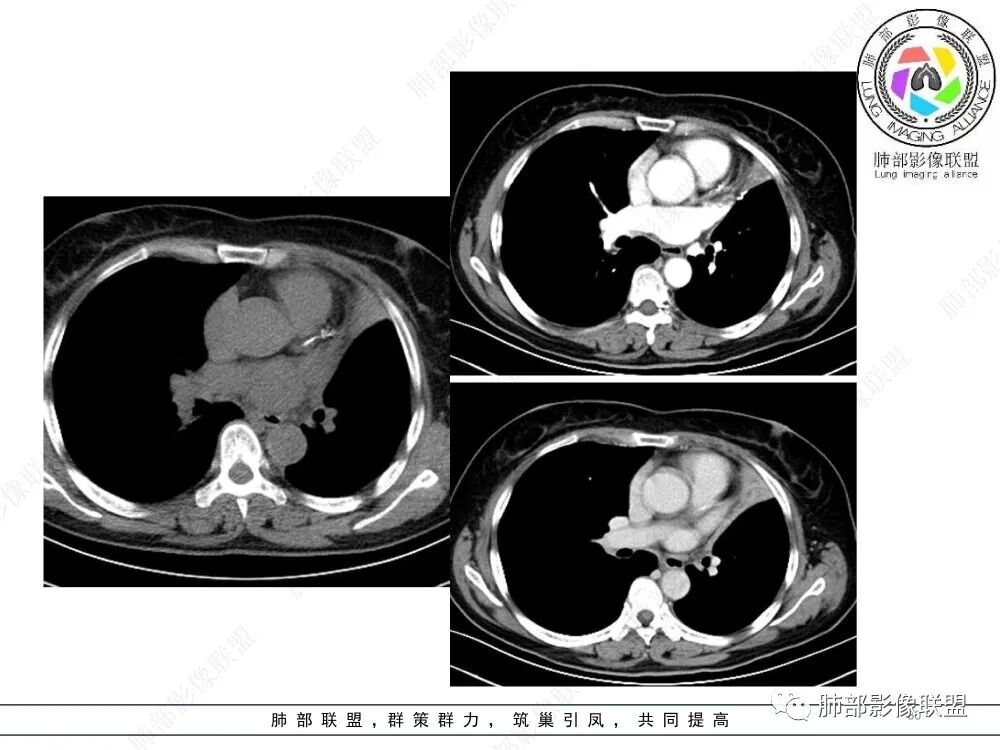

2、影像表现:正常肺背景,左肺上叶支气管腔内占位,上叶支气管截断,远端肺组织不张,强化差异衬托出肺门区结节影或块状影。增强扫描腔内占位轻中度不均匀强化,可见坏死,远端粘液栓,局部肺动脉受压、侵犯,纵膈淋巴结无明显肿大,无胸腔积液。

①鳞癌多见于中老年吸烟男性,有肺气肿背景,由于肿瘤容易向腔内生长,因此易较早阻塞支气管致肺不张,肿瘤易形成中心坏死或空洞,坏死范围较大时影像上呈“湖泊样”改变。

②腺样囊性癌、粘液表皮样癌属于涎腺肿瘤,多见于40-60岁人群,男女发病率无显著差异,与吸烟无关,发病部位前者以气管及主支气管多见,后者以叶段支气管多见,多表现为支气管腔内占位,强化程度较轻,二者影像表现相似,常常较难鉴别。

③类癌属于低度恶性神经内分泌肿瘤,发病年龄13-70岁,成年人中以中央型类癌多见,影像表现为支气管腔内的圆形或卵圆形结节,边缘光整,也可浅分叶,可完全位于支气管腔内,也可以病变管腔内的病变只占病变的一小部分,大部分位于管腔外,称为“冰山征”,少数病例可沿支气管腔内长轴生长,呈指套样改变,可伴有小部分位于腔外,类似部分鳞癌的表现,但类癌血供较鳞癌丰富,多数呈显著较均匀强化,不典型类癌可呈不均匀强化,肿块较大时可阻塞支气管导致肺不张。

④小细胞肺癌属于高度恶性神经内分泌肿瘤,好发于吸烟男性,多数小细胞癌影像表现较典型,表现为肺门旁或外周边缘膨隆、边界清楚的软组织结节或肿块,由于肿瘤组织坏死不彻底,常表现为“沼泽样”坏死区,较早出现肺门和纵膈淋巴结转移,有“娘小崽大”的特点。纵隔淋巴结融合,可形成“冰冻纵膈”。小细胞癌侵袭力强,容易包埋血管形成“血管包埋征”,肿瘤沿支气管浸润时可见病灶呈鸭蹼和腊肠样凸起,相较于鳞癌而言,小细胞癌导致的阻塞性肺炎常常较轻,较少合并肺不张,少见合并胸水。

就本例而言,患者为女性,无肺气肿背景,未提及吸烟史,影像上强化程度偏轻,未见湖泊样坏死,尽管中央型肺癌中以鳞癌最多见,且造成完全阻塞及肺不张,但在女性患者诊断鳞癌仍需谨慎。支气管腔内结节,强化程度轻,涎腺肿瘤需要考虑,不典型类癌也不能除外。女性患者,未提及吸烟史,尽管未见纵膈淋巴结明显肿大,但支气管明显相关,小细胞肺癌亦应当重点排除。